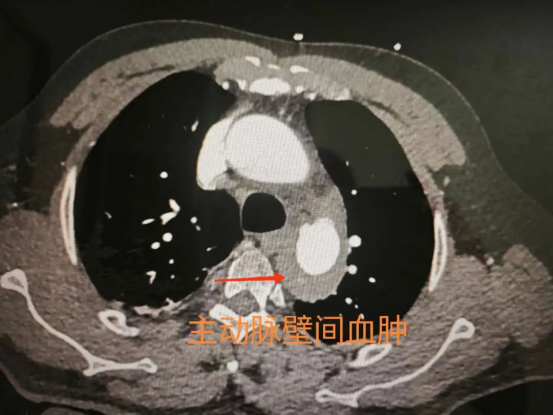

▲术前壁间血肿影像学图片

随着冯伯病情稳定,对多种疾病的根治治疗提上议程。广医一院心血管内科主任陈爱兰主持全科讨论,结合影像学特点与患者个体情况,最终确定了"主动脉腔内隔绝术+左锁骨下动脉支架置入术"的微创治疗方案。